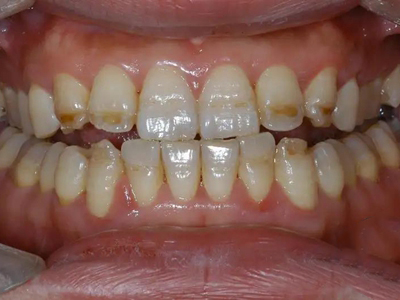

牙釉质发育不全牙齿变薄图

牙釉质发育不全患者的牙齿有色泽和透明度改变,表面出现白垩色釉质,同时牙齿顶端变透明、变薄,但患者可能无敏感、疼痛等自觉症状。